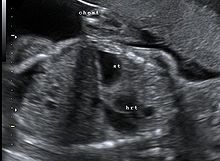

Congenital diaphragmatic hernia: coronal obstetric ultrasound (head to right of image, thorax centre, abdomen left) shows the stomach and heart both within the thorax.

This condition can often be diagnosed before birth and fetal intervention can sometimes help, depending on the severity of the condition.[5] Infants born with diaphragmatic hernia experience respiratory failure due to both pulmonary hypertension and pulmonary hypoplasia. The first condition is a restriction of blood flow through the lungs thought to be caused by defects in the lung. Pulmonary hypoplasia or decreased lung volume is directly related to the abdominal organs presence in the chest cavity which causes the lungs to be severely undersized, especially on the side of the hernia.